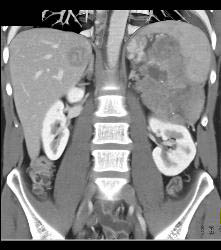

GIST Tumor With Ulceration